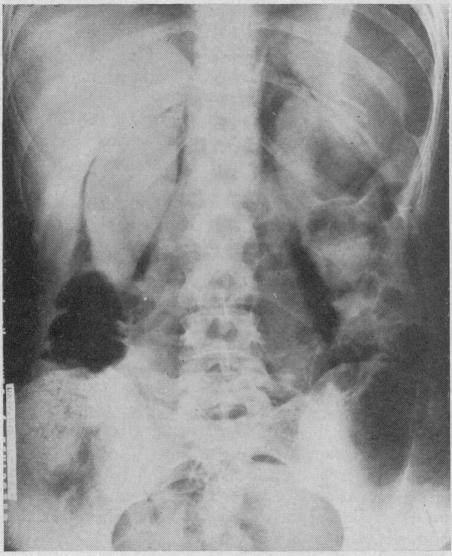

Extraperitoneal pneumography; a preliminary report.

The presence of a gas in the retroperitoneal tissues makes possible a radiologic visualization of retroperitoneal organs and masses. Retropneumoperitoneum is accomplished by the injection of oxygen at low pressure into the tissues lying between the coccyx and the rectum. The technique of injection is simple and no complications have occurred with the first 30 cases. This method is particularly useful in outlining the kidneys and adrenal glands.